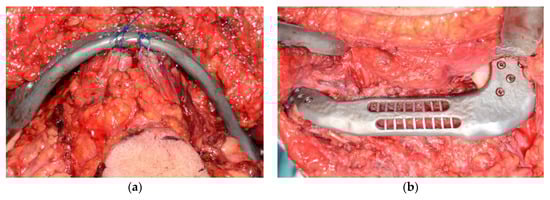

2.2. Surgical Procedure